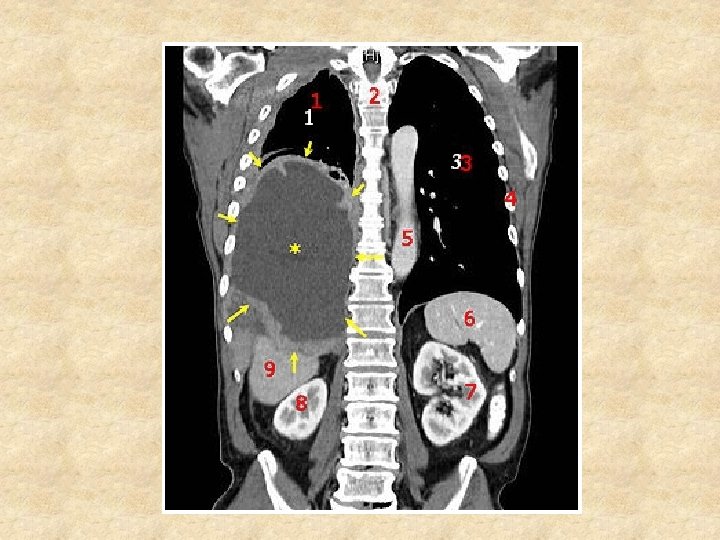

Frontal or Coronal Plane • http: //www. madsci. org/~lynn/VH/coronal. ht ml

Frontal Plane Imaging